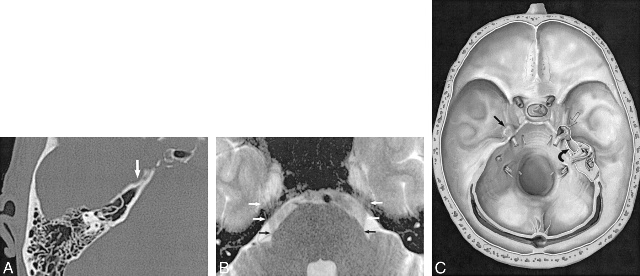

3. 三叉神经根受压的判断观察血管与三叉神经的解剖关系,由于侧卧位可引起小脑动脉移位,因此距三叉神经根1~2mm的血管均视为与神经有接触,特别是神经上有压迹或神经被推移和扭曲者更是可靠证据。下面部疼痛患者,是由于三叉神经根上前或后部受小脑上动脉压迫;而上部疼痛者则为神经根下外部受小脑前下动脉压迫。

4. 微血管减压确认血管压迫三叉神经根后,用长柄微型剥离子把血管从神经上分开,在三叉神经前方垫入小块明胶海棉。取1cm×0.5㎝涤纶片,两端用剪刀修成锐角,在明胶海绵和三叉神经根之间插入,并向后环绕神经,用一枚银夹把涤纶片两端对合,使之如“领套”状围绕桥脑旁的三叉神经, 以便与周围的血管隔离。也可用涤纶片衬垫在血管和神经之间,生物胶固定之。

微血管减压手术操作注意的问题:(1)一般不会损伤感觉根,可保留三叉神经的生理功能;(2)压迫血管多为动脉,而不管那一条动脉压迫,其动脉的压迫位置多在后根背侧(后侧)的蛛网膜下腔成袢状或紧缩状(基底动脉)压迫,为此,在寻找辨认致病压迫血管时,应首先用显微剪或显微膝状镊,仔细将增厚粘连的蛛网膜打开,并充分游离,显露出三叉神经感觉根的颅内段,尤其应将感觉根的入根区显露清楚(因此区往往是基底动脉和小脑前下动脉施压之处),确认后根上没有潜伏贴附血管后再剪切,以防切断血管,而导致严重后果。切断的部位在入根区0.5-1cm处;(3)对小脑上动脉形成袢状压迫者,行血管悬吊减压,效果良好(9);(4)在探查三叉神经感觉后根时,手术操作应尽量轻柔,为避免过多的刺激和损伤面神经与听神经,可先用一棉片保护面、听神经,以防止术后暂时性面部神经分布区域感觉减退及术后听力减低;(5)减压材料中,涤纶棉较涤纶片为好,因其刺激性小,Teflon棉则更好。(6)对打开的乳突气房,要用骨蜡严密封闭,以防止术后脑脊液鼻漏的发生;(7)冲洗桥小脑角处,如果用过大压力和冷生理盐水,可引起术后头痛、头晕、恶心或呕吐等反应,因此应该用等体温生理盐水轻柔冲洗;(8)切开的硬脑膜,应严密缝合,若张力较大,不能达到严密缝合时,可在切口周围切下一小块肌片,填塞后缝合固定,再覆盖明胶海绵,可减少和避免术后切口下积液、脑脊液漏的发生。